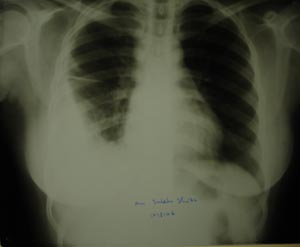

View Right lower zone pleural effusion

Right lower zone pleural effusion